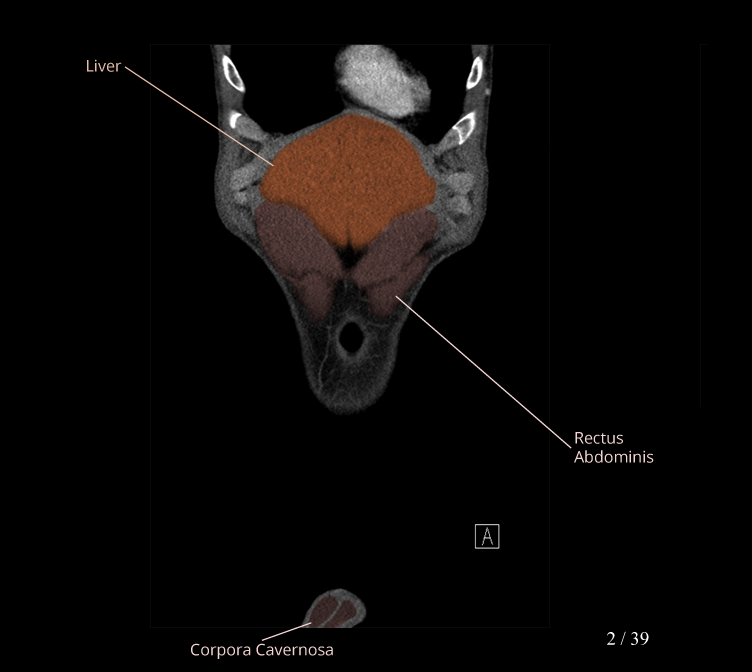

Anatomy Modules

Labeled radiographs and scrollable CT/MRI series teaching radiologic anatomy with a level of detail appropriate for medical students and junior residents.

Body

Covers abdominal CT anatomy.